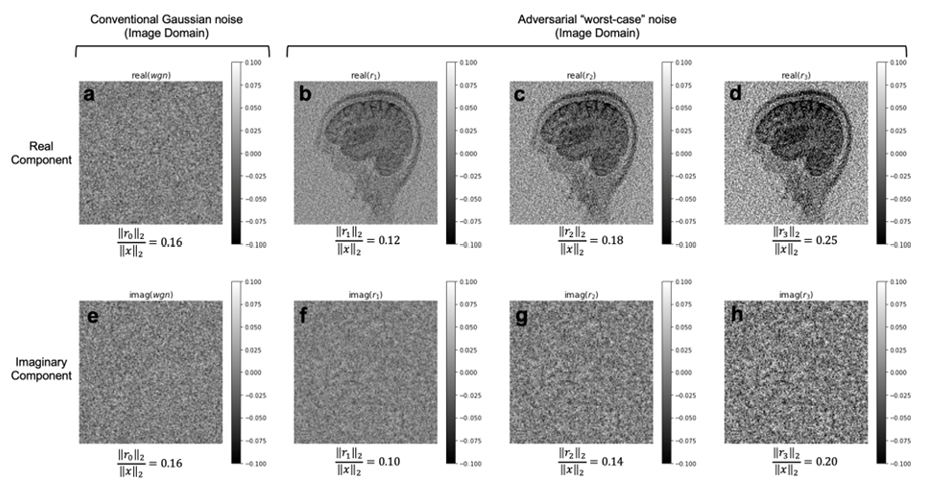

We trained AUTOMAP models to study two properties of training datasets, robustness to FOV artifacts and adversarial noise. The training images were 2D T1-weighted brain MR images acquired at 3 T collected from the MGH-USC Human Connectome Project (HCP) public dataset4. For the FOV experiments, we needed to curate two datasets, one with a single FOV (random samples shown in Fig 1a) and one with multiple FOVs (random samples shown in Fig 1b). Fig 1c was used to showcase artifacts from the different models in Fig 2 and discussed in the results. To study the robustness to adversarial noise and the role of numerical properties of a dataset, the adversarial noise was generated using a gradient ascent with momentum perturbation search algorithm3. The original AUTOMAP was trained to output positive, magnitude images. The adversarial noise pushed this boundary to generate negative and complex-valued noise in the image domain. When applied in the k-space domain, the numerical properties pushed AUTOMAP beyond its reconstruction capabilities leading to artifacts. In Fig 3, we show the adversarial noise is highly structured and contains negative values. Instead of training on positive, magnitude-only images, we added randomized constant offsets (between -0.1 and +0.1) to the training images and retrained AUTOMAP. We show the results of both these models in Fig 4.

The top row in Fig 2 demonstrates what artifacts arise when a model trained on a single FOV is tested on an out-of-distribution FOV in the image domain. All conditions, without noise (Fig 2a), Gaussian noise (Fig 2b), and Poisson noise (Fig 2c), display artifacts (particularly in the dark image background region). After retraining AUTOMAP with multiple FOVs, under both noiseless and noise-applied conditions, the artifacts were significantly reduced (bottom row Fig 2 d-f). We tested and demonstrated how important the role of training data augmentations is through something as simple as incorporating multiple FOVs in the training data. In a clinical setting, these same artifacts could lead to a misdiagnosis or a delay as the clinical practitioners may not be aware where the fault occurred. We also demonstrate the role of the numerical properties of a training dataset and how artifacts introduced by adversarial noise can be avoided. Fig 4a (top row) demonstrates artifacts that arise from adversarial noise. After training a network on images that contain negative offsets due to the adversarial noise consisting of negative values, the retrained AUTOMAP model doesn’t contain the same artifacts in Fig 4b (bottom row). If adversarial noise is a concern, we demonstrate it is important to study the numerical properties of the dataset and augment it appropriately so the model can generalize in practice.

Fig 3. Adversarial noise exhibits highly structured features not observed in natural statistical noise. The real (top row, a-d) and imaginary (bottom row, e-h) components of additive noise are displayed in the image domain. The engineered adversarial noise samples shown (b-d and f-h) are highly structured unlike natural noise and we observe an unnatural phase bias as manifested by the dissimilarity between the real (b-d) and imaginary (f-h) components.